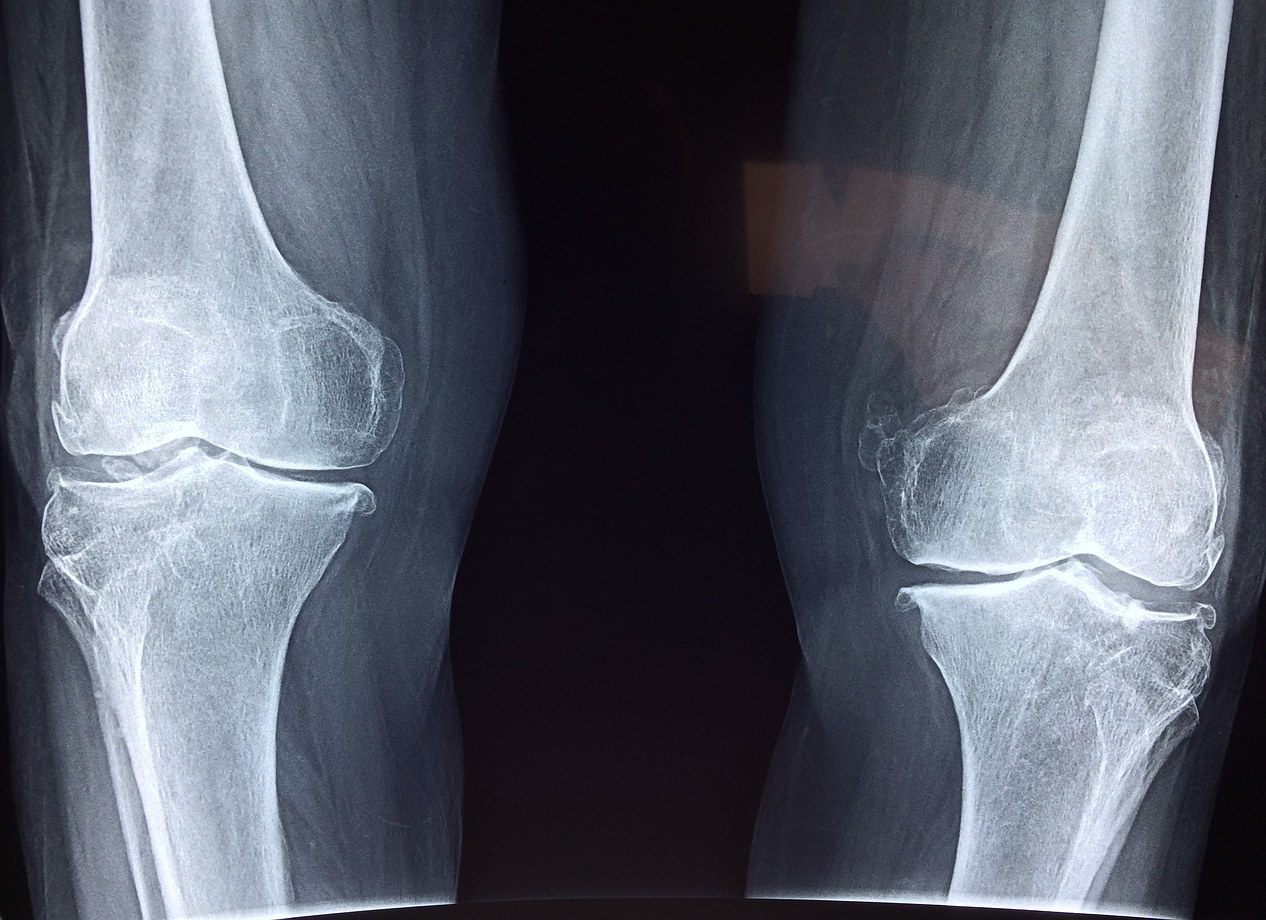

통풍은 보통 관절에 요산 결정체가 축적되어 발생하는 염증성 질환입니다.

주로 엄지발가락 관절에 많이 발생하지만, 발목과 무릎, 손목 등 다른 관절에서도 발생할 수 있습니다.